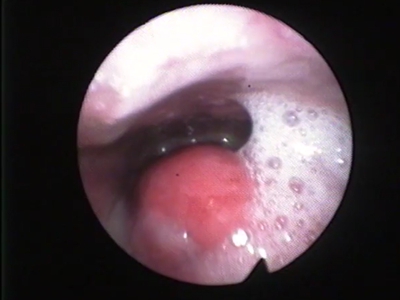

急性会厌炎起病急骤,有畏寒、发热、头痛等全身不适,多数患者体温在38-39℃。以剧烈的咽喉疼痛为主要症状,吞咽时加剧,重者饮水呛咳、流涎。喉镜下可见会厌舌面黏膜充血,高度肿胀水肿呈圆球状如卷曲香肠,肿胀可偏于一侧,偶见有黏膜溃疡。